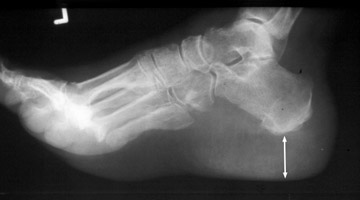

Single lateral radiograph of the foot with a grossly enlarged and thickened calcaneal heel pad. Although not pathognomonic, a heel pad thickness greater than 23 mm may indicate acromegaly. The overabundance of growth hormone in acromegaly causes, among other things, gradual enlargement of hands, feet, and exaggeration of facial features. Not limited to the bones, however, enlargement of other parts of the body, such as the soft tissues of the heel may help to diagnose acromegaly.